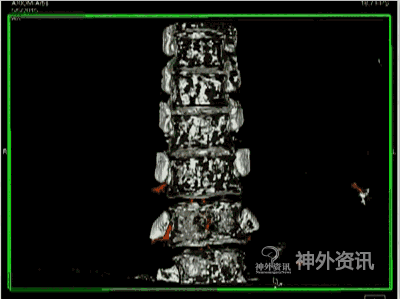

图5: 下颈段脊髓血管畸形,↑示畸形血管团。A、B. 2D-DSA;C. 3D-DSA;D~F. 静态最大密度投影(MIP)冠状位、矢状位和轴位融合影像。

图5: G. 动态旋转MIP融合影像。

图5: H~J. 静态双容积重建冠状位、矢状位和轴位融合影像。

图5: K. 动态双容积重建冠状位融合影像。

图5: L. 动态双容积重建矢状位融合影像。

图5: M. 动态双容积重建轴位融合影像。